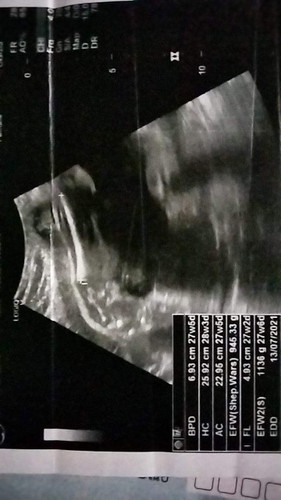

กำหนดคลอด 11ก.ค.

เหมือนจะเป็นผู้ชาย แต่โฟกัสภาพนี้ไม่ชัดเจน เพราะโฟกัสที่กระดูกต้นขาเจ้าตัวเล็กค่ะ ตรงเพศน้องเลยค่อนข้างเบลอมาก รออัลตราซาวด์รอบหน้าค่ะคุณแม่ หรือรอลุ้นตอนคลอดเลยค่ะ😊